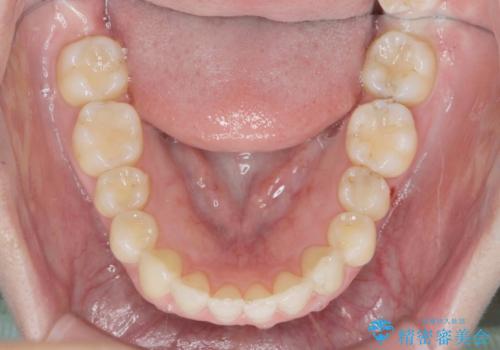

カリエール・マイクロインプラントを併用した歯の突出を改善する大きな遠心移動

- 口が閉じづらく、突出し歯が出っ歯に見えてしまうことの改善を求めて来院されました。

通常このような場合、抜歯してのワイヤー矯正治療も選択肢に入りますが、患者様の強い希望により抜歯を行わずマウスピースによる治療を選択しました。

カリエール・マイクロインプラントを用い、時間はかかりましたが大きく歯の後方移動が達成され、前歯の見た目が大きく改善されました。